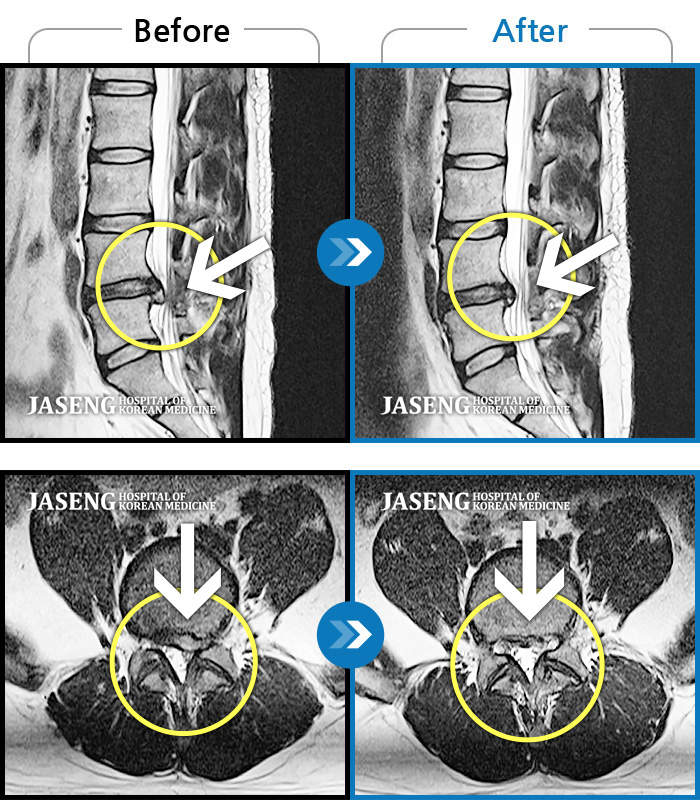

어떠한 자세를 취해도 통증이 있고 왼쪽 엉덩이, 다리 통증으로 잠을 자주 깬다.